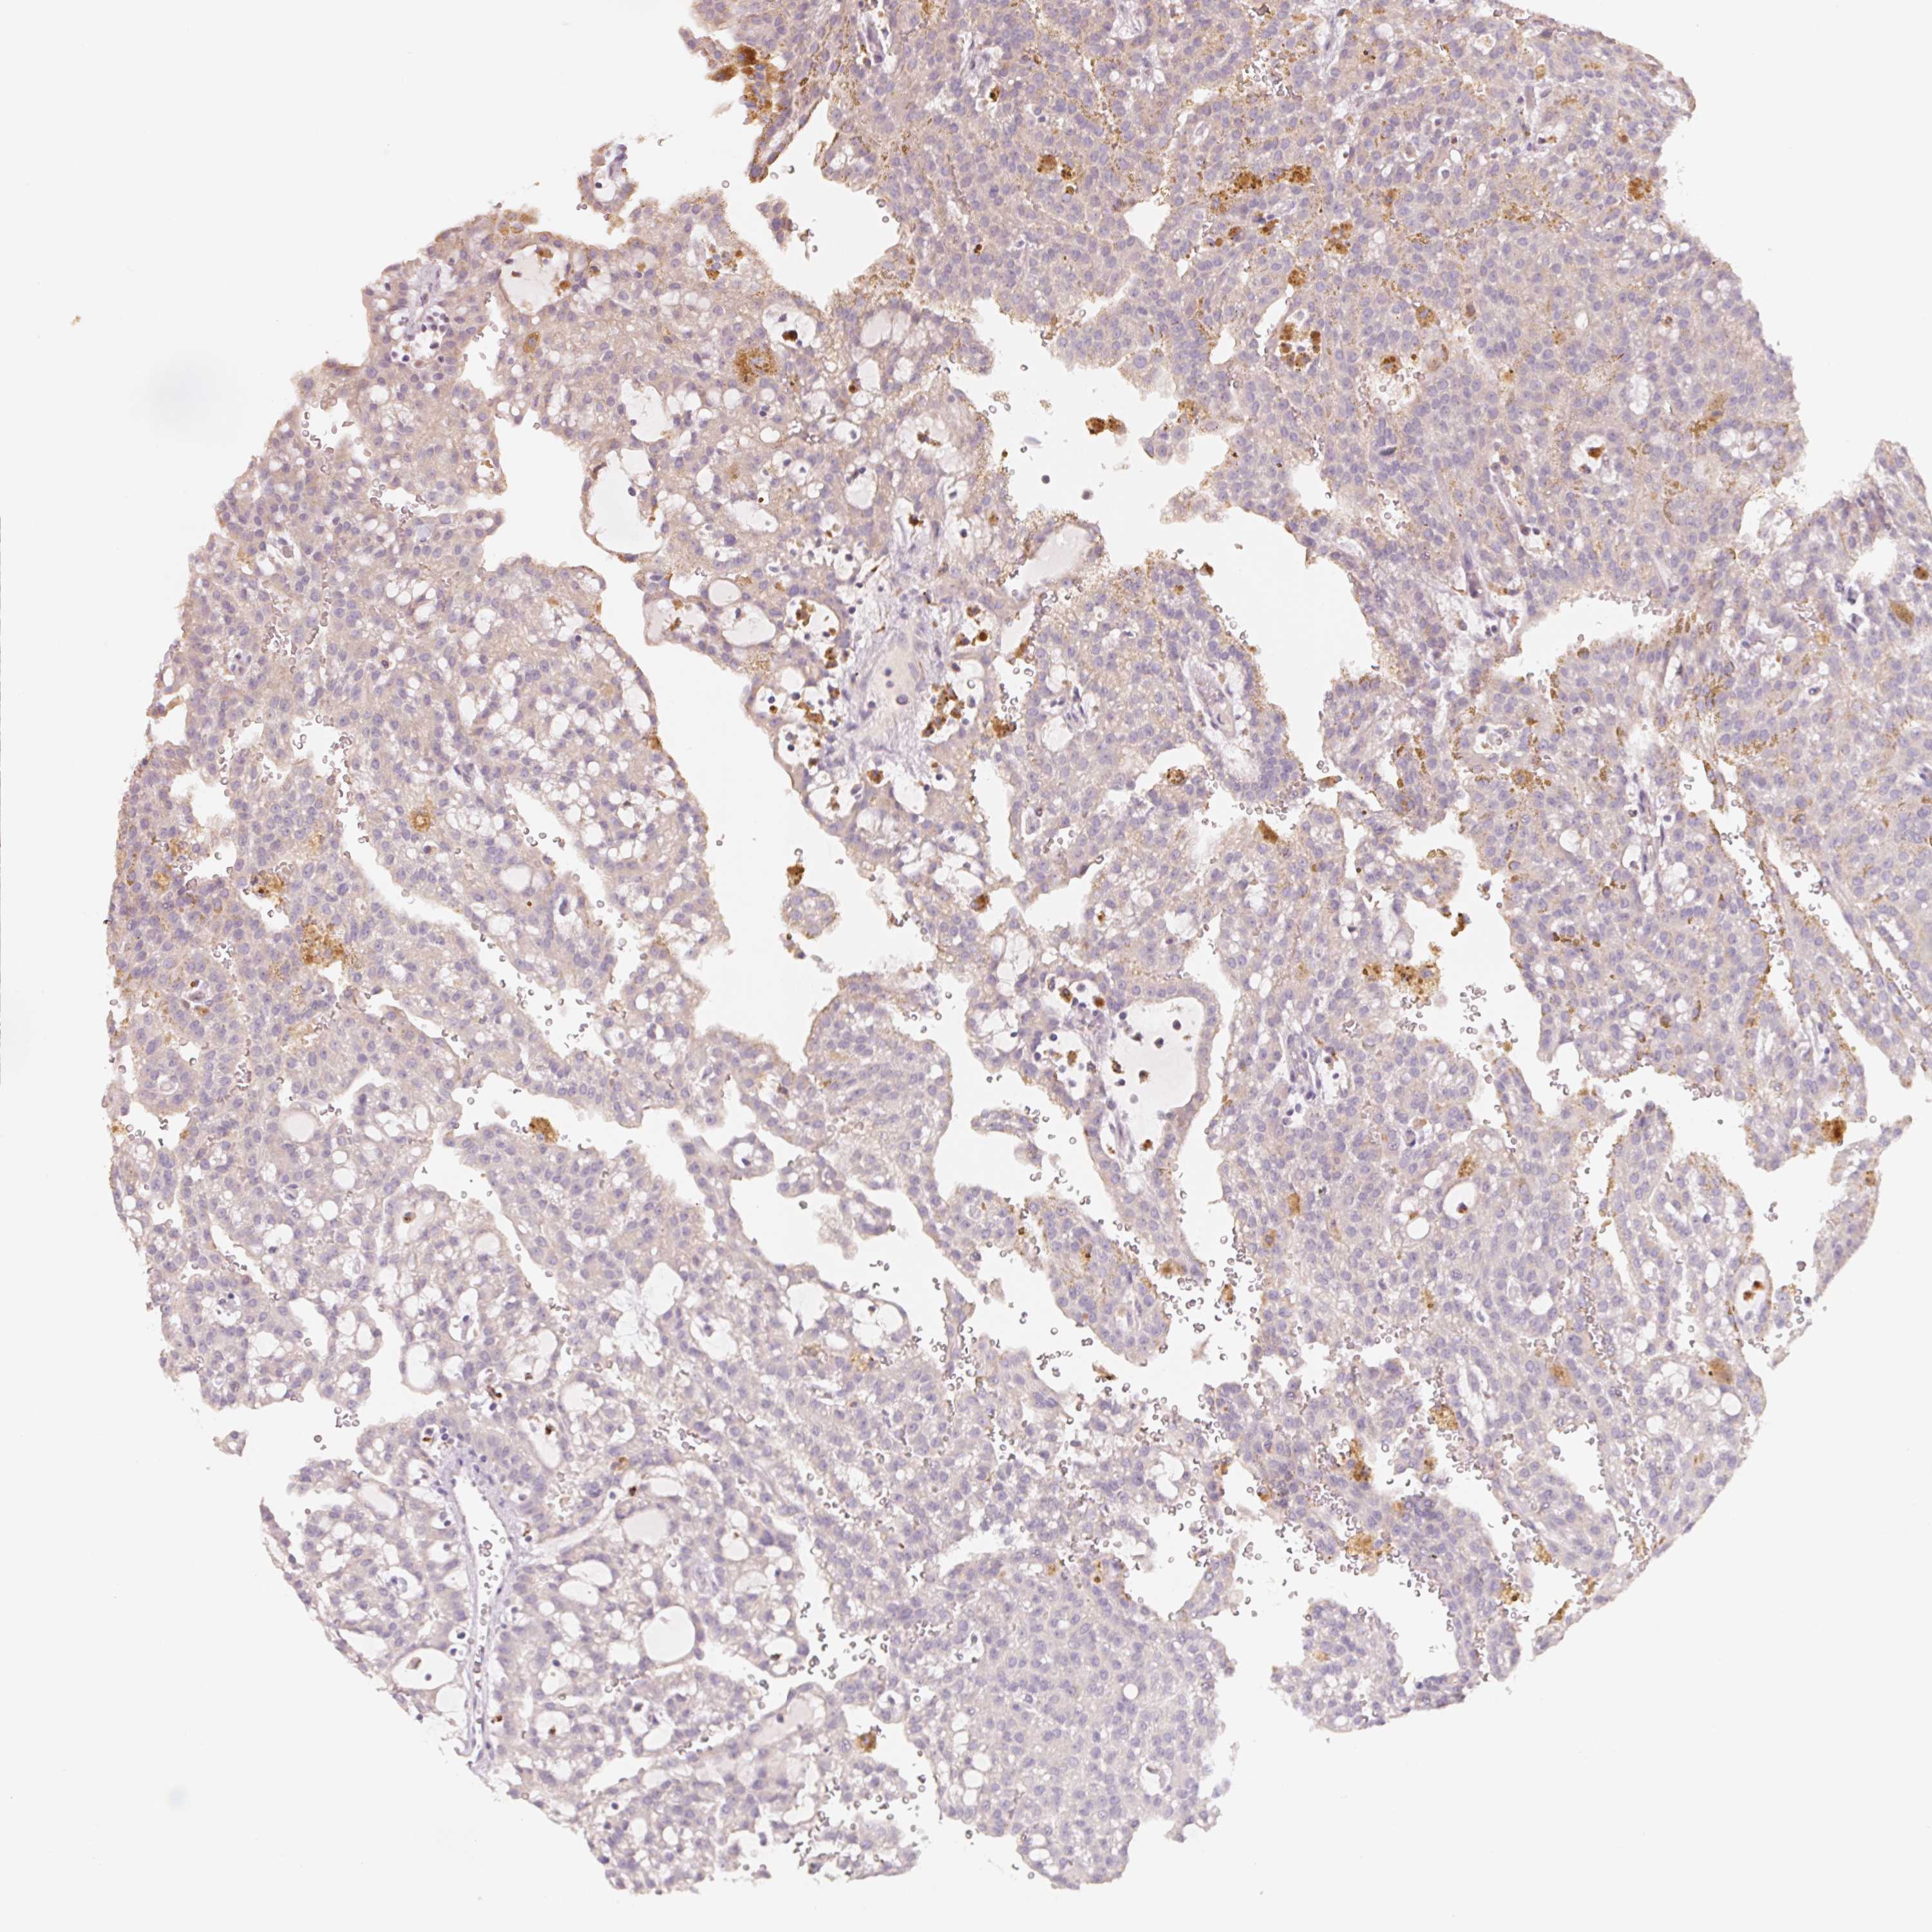

KIDNEY RENAL CLEAR CELL CARCINOMA (VALIDATION) - Interactive survival scatter ploti

The Survival Scatter plot shows the clinical status (i.e. dead or alive) for all individuals in the patient cohort, based on the same data that underlies the corresponding Kaplan-Meier plots. Patients that are alive at last time for follow-up are shown in blue and patients who have died during the study are shown in red.

The x-axis shows the expression levels (FPKM) of the investigated gene in the tumor tissue at the time of diagnosis. The y-axis shows the follow-up time after diagnosis (years). Both axes are complimented with kernel density curves demonstrating the data density over the axes. The top density plot shows the expression levels (FPKM) distribution among dead (red) and alive patients (blue). The right density plot shows the data density of the survived years of dead patients with high and low expression levels respectively, stratified using the cutoff indicated by the vertical dashed line through the Survival Scatter plot. This cutoff is automatically defined based on the FPKM cutoff that minimizes the p-score. The cutoff can be changed by dragging the vertical line or by entering a cutoff value in the square labeled "Current cut-off".

Under the Survival Scatter plot the p-score landscape (black curve; left axis) is shown together with dead median separation (red curve; right axis). Dead median separation is the difference in median mRNA expression between patients who have died with high and low expression, respectively. It is calculated as follows: median FPKM expression of dead patients with high expression - median FPKM expression of dead patients with low expression. This is intended to aid the user in visually exploring custom cutoffs and the associated p-scores and dead median separation.

Individual patient data is displayed and can be filtered by clicking on one or more of the category buttons on the top of the page. Categories describing expression level and patient information include: high, low, alive, dead, female, male and tumor stages. The scale of the x-axis can be toggled between linear and log-scale by clicking on the "x log" button. Mouse-over function shows TCGA ID, patient information and mRNA expression (FPKM) for each patient.

& Survival analysisi

Kaplan-Meier plots summarize results from analysis of correlation between mRNA expression level and patient survival. Patients were divided based on level of expression into one of the two groups "low" (under cut off) or "high" (over cut off). X-axis shows time for survival (years) and y-axis shows the probability of survival, where 1.0 corresponds to 100 percent.

TREH is validated prognostic, high expression is favorable in Kidney Renal Clear Cell Carcinoma (validation)

Best expression cut offi

Based on the FPKM value of each gene, patients were classified into two groups and association between prognosis (survival) and gene expression (FPKM) was examined. The best expression cut-off refers the FPKM value that yields maximal difference with regard to survival between the two groups at the lowest log-rank P-value. Best expression cut-off was selected based on survival analysis .

When clicking on this number, the vertical dashed line indicating cut-off, the interactive survival plot, and the Kaplan-Meier curve will be adjusted to show results based on the best expression cut-off.

: 1.33

TCGA RNA samplesi

RNA-seq data is reported as average FPKM (number Fragments Per Kilobase of exon per Million reads), generated by the The Cancer Genome Atlas (TCGA) .

Normal distribution across the dataset is visualized with box plots, shown as median and 25th and 75th percentiles. Points are displayed as outliers if they are above or below 1.5 times the interquartile range. FPKM values of the individual samples are presented next to the box plot.

Average pTPM 2.1

Number of samples 100